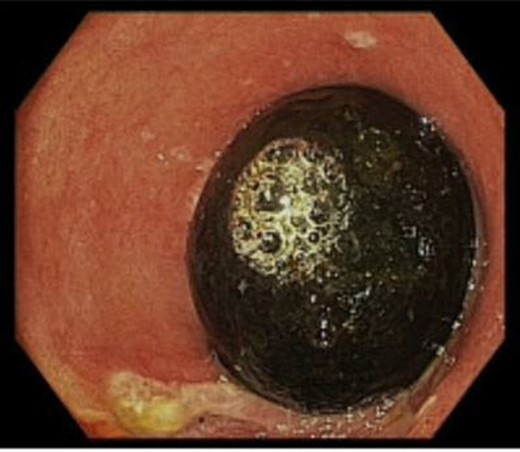

Abdominal sonography revealed a distended gall bladder filled with sludge and a grossly distended stomach. Upper GI endoscopy uncovered residual food, and a peeping gallstone impacted distal to the pyloric ring, indicating BS (Fig. 1). Endoscopic disimpaction was unsuccessful. Computed tomography and MR cholangiography confirmed a large gallstone, causing a cholecystoenteric fistula with significant inflammatory changes and gastric outlet obstruction (Fig. 2).

(A) CT scan and (B) MRCP showing a hugely distended stomach with a gallstone obstructing the pylorus.